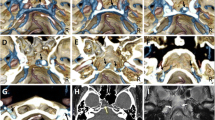

A representative case of the anterior condylar vein (ACV) bridging vein (BV). Axial view of the slab MIP images from contrast-enhanced cone-beam CT shows that the transverse medullary vein (arrow in (a)) drains into the ACV (double arrows in (c)) in the hypoglossal canal via the ACV BV (arrowheads in (a)–(c)). Star shows the right vertebral artery

A representative case of the jugular foramen (JF) bridging vein (BV). Axial (a) and coronal (b) view of the slab MIP images from contrast-enhanced cone-beam CT show that the transverse medullary vein (arrow in (a) and (b)) drains into the inferior petrosal sinus (double arrows in (b)) and sigmoid sinus (not shown) via two JF BVs (white and black arrowheads). Star shows the left vertebral artery running close to the opposite side

A representative case of the marginal sinus (MS) bridging vein (BV). Axial (a) and coronal (b) view of the slab MIP images from contrast-enhanced cone-beam CT show that the transverse medullary vein (arrow in (a)) and lateral medullary vein (arrow in (b)) drains into the MS (double arrows in (a) and (b)) via two MS BVs (white and black arrowheads). Star shows the right vertebral artery

A representative case of the suboccipital cavernous sinus (SCS) bridging vein (BV). Axial (a) and coronal (b) view of the slab MIP images from contrast-enhanced cone-beam CT show that the lateral medullary vein (arrow in (b)) drains into the SCS (double arrows in (a) and (b)) via a SCS BV (arrowhead). Star shows the right vertebral artery

A representative case of the cerebellomedullary cistern (CMC) bridging vein (BV). Axial (a) and sagittal (b) view of the slab MIP images from contrast-enhanced cone-beam CT show that the transverse medullary vein (arrow in (a)) and posterior spinal vein (arrow in (b)) drain into the marginal sinus (double arrows in (a) and (b)) via a CMC BV (arrowhead), which is the posteromedian BV running through the CMC. Star shows the right vertebral artery